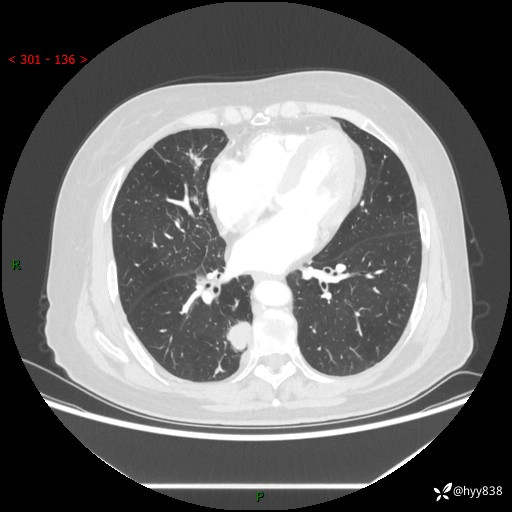

胸部CT肺窗(平扫外院)